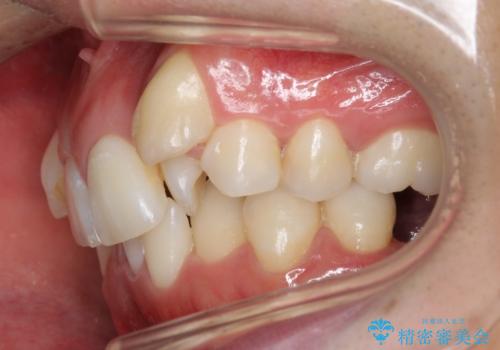

- 八重歯を主訴に来院。

下の歯がないところに、奥歯が倒れこんでいたため、矯正治療で倒れこんだ歯を起こして、インプラントを植立しました。

上の前歯が下の前歯に大きく重なっており、過蓋咬合を呈していました。